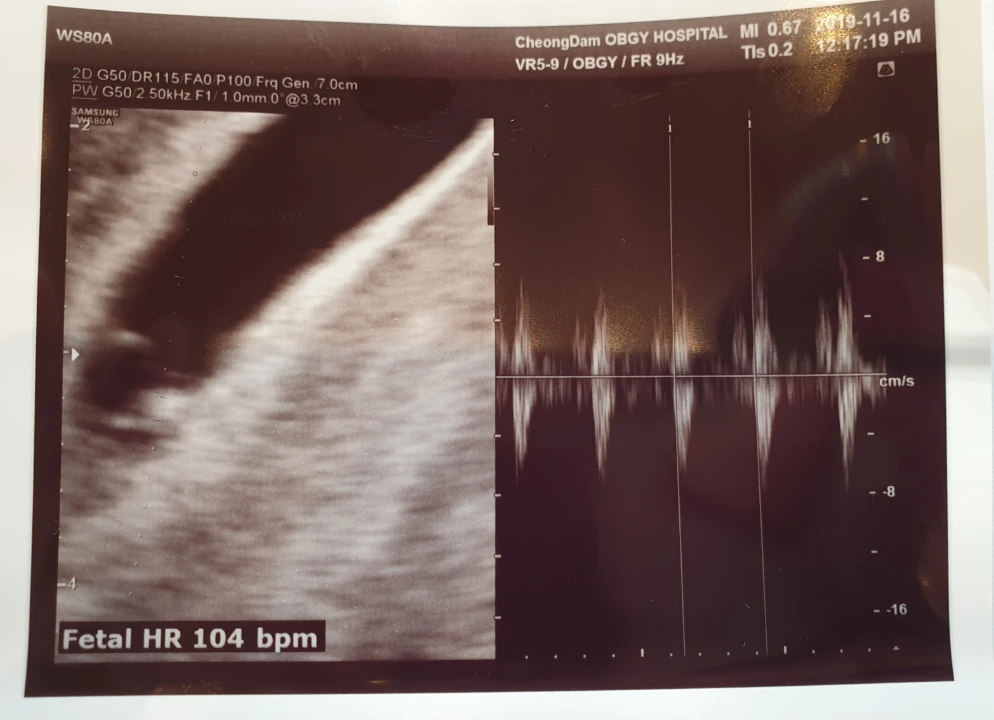

어제는 초음파를 찍으러 강남을 갔다. 주말 오전 도로는 부자의 만남을 모질게도 밀어냈고, 아내의 얼굴에서 웃음이 사라졌다. 엎친 데 덮친 격으로 병원을 코 앞에 두고 길을 잘못 들어 영동대교로 들어서면서는 나도 모르게 눈물이 나왔다. 한강을 건널 수밖에 없는 나의 운명과, 예약 마감 시간을 훌쩍 넘긴 시계 숫자열과, 2시간이 지나며 깊은 한숨만 쏟아내는 아내가 나를 절망케 했다. 얼마나 당황했던지 "잘못했어요. 정말 잘못했습니다."라고 아내에게 울먹이기까지 했다. 거의 울다시피 차를 몰아 병원에 도착했지만 주차가 문제였다. 뭔 놈의 병원에 차가 이리도 많은지. 대한민국 출산율은 여기서 다 올리나 싶었다. 아내를 먼저 들여보낸 후 동네를 한 바퀴 돌고 병원 앞에서 한참을 엉거 주춤대고 있으려니까 그제야 주차 대리인이 와서 안 들어갈 거냐고 묻는다. 어이가 없었지만 죽어라 병원 계단을 뛰어올랐다. 아내는 다행히 예약 없는 의사에게 진료를 받았지만, 나는 2mm짜리 내 아이가 가쁘게 내쉬는 심장 소리를 놓치고 말았다. 나오면서 주차 대리비를 내는데 어찌나 아쉽고 짜증이 나던지 이래서 아이가 개입된 일에 어른들이 물불 안 가리는구나 싶었다. 그래도 5주 5일 정도 된 (실제 나이는 알 수 없었다) 내 아이가 104 bpm이나 되는 심장을 벌써 갖고 안전하게 착상하고 있다니 대견했다. 어린 녀석이 벌써 안 떨어지려고 안간힘을 쓰며 버티고 있구나. 역시 내 새끼다.